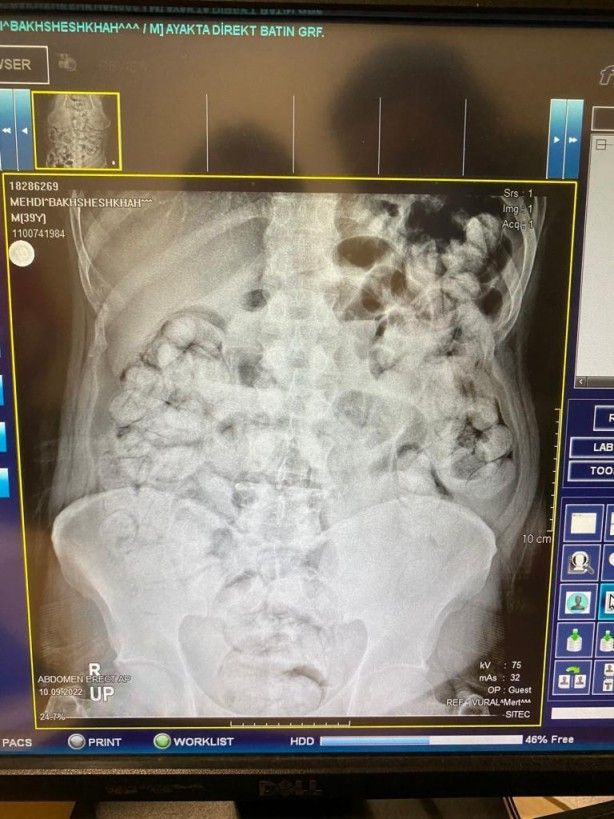

Çekilen röntgen filmlerinde şüphelilerin vücutlarında 62 kapsül eroin ve 210 kapsül afyon sakızı olduğu tespit edildi.

Röntgen çekimlerinde uyuşturucu kapsüllerinin şüphelilerin neredeyse iç organlarının her tarafına yayıldığı belirlendi. Doktor ve polis, vücutta tek seferde bu kadar yüklü miktarda uyuşturucu görmenin şaşkınlığını yaşadı. Gözetim altına alınan ve röntgenleri çekilen şüphelilerin vücudundan parça parça dışkılama yöntemi ile uyuşturucular çıkarıldı. Zanlıların hastanedeki işlemleri sürerken Narkotik Suçlarla Mücadele Şubesi ekiplerinin teknik ve fiziki takiplerinde, benzeri yöntemle yine aynı güzergahtan uyuşturucu götürüleceği bilgisi alındı. Bunun üzerine uygulama noktasında durdurulan bir otobüste, koltukta oturma şekilleri ile hal ve hareketlerinden şüphelenilen İran uyruklu Masoud T. ve Soleman O. gözaltına alınıp hastaneye götürüldü.

Yapılan kontrollerde ve röntgen çekimlerinde, şüphelilerin vücutlarından 411 kapsül afyon sakızı olduğu belirlendi. İlk operasyonda ve ikinci operasyonda yakalanan zanlıların, uyuşturucuları bugüne kadar rastlanılmayan kolonoskopi yöntemiyle vücutlarına soktukları değerlendirildi. Şüpheliler hastane kontrollerinde ise vücutlarına uyuşturucunun baygınken konulduğunu ve ne kadar miktarda uyuşturucunun vücutlarına doldurulduğunu bilmediklerini iddia etti. Doktor nezaretinde 5 gün süren dışkılama yöntemiyle vücutlarından 6 kilo 955 gram ağırlığında 683 kapsül uyuşturucu çıkartılan 5 şüpheli, emniyete götürüldü. Buradaki işlemlerinin ardından adliyeye çıkarılan zanlılar tutuklandı.